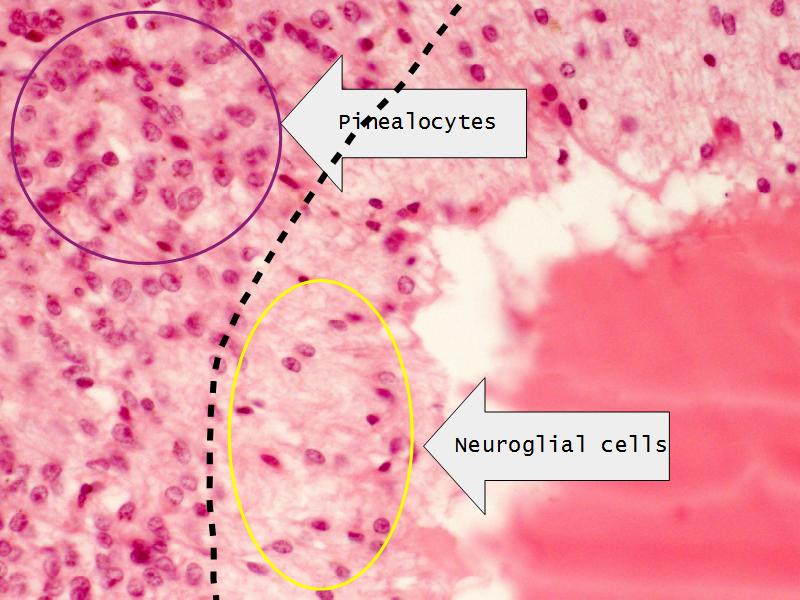

- Slide 34: Pineal gland

Pineal Gland